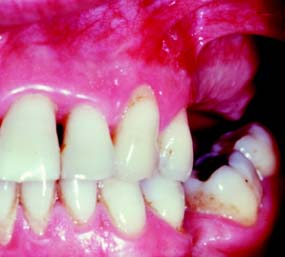

The laterally positioned pedicle graft40,41 (Fig. 6-14) is used for an area of recession or lack of attached gingiva on a single tooth when there are adequate amounts of keratinized gingiva in adjacent teeth or edentulous spaces. Although several studies have proposed techniques in which free (detached) autogenous gingival grafts are used for root coverage,42-44 the pedicle graft can be a more predictable treatment because of maintenance of the blood supply to the pedicle.

Fig. 6-14 Laterally positioned pedicle graft. A and B show localized recession around the left mandibular central incisor. The lateral incisor has an adequate band (width) of keratinized tissue, so it is suitable as a donor site. C, Bed preparation of the recipient site. An incision is made obliquely toward the site. D, Releasing incision at the distal of the donor site. The graft is rotated into position over the recipient site. E, Flap sutured in position. A free autogenous gingival graft may be used to cover the donor site. F, The healed graft. There is almost always some loss of attachment at the donor site (average, 1 mm).

The recipient site is prepared by excising 1 to 3 mm of split-thickness marginal gingiva bordering the recession area. At the donor site, oblique vertical incisions are placed in the mucosa as far apically as possible to ensure adequate blood supply for the graft. The apical area of the donor tissue is made wider than the coronal area. The flap is mobilized and placed on the recipient site and sutured into place. A free gingival graft may be needed to cover the donor site. A surgical dressing is placed over the site.

There are certain limitations of laterally positioned pedicle grafts: